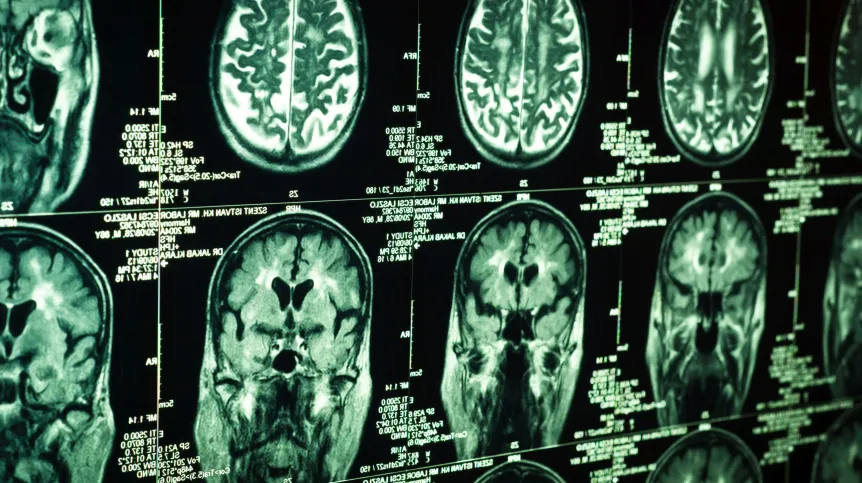

Badania nad nową metodą dostarczania leków do mózgu przeprowadzili włoscy naukowcy z Università Cattolica del Sacro Cuore/Fondazione Policlinico Universitario A. Gemelli IRCCS w Rzymie we współpracy z Uniwersytetem w Salerno (DOI: 10.1002/adma.202513858). Chodzi o podawane w formie aerozolu do nosa maleńkie cząsteczki złota, które działają jak nośniki, pozwalające lekowi dotrzeć wprost do mózgu.

Zdaniem autorów badania podawane donosowo nanocząsteczki złota mogłyby znaleźć zastosowanie na przykład w leczeniu zaburzeń psychicznych i chorób neurodegeneracyjnych. Metoda została już opatentowana.

Badania wykazały, że możliwe jest bezpośrednie hamowanie aktywności enzymu (kinazy syntazy glikogenu 3 beta, GSK-3β) odgrywającego kluczową rolę w rozwoju chorób neurodegeneracyjnych i zakaźnych mózgu. Można tego dokonać bezpośrednio w mózgu, podając donosowo lit z pomocą złotych nanocząsteczek.

Podczas badań na zwierzętach udało się - dzięki zastosowaniu złotych nanocząsteczek - zahamować aktywność enzymu GSK-3β w hipokampie i przywrócić pamięć zaburzoną w eksperymentalnym modelu choroby Alzheimera, bez wystąpienia działań niepożądanych.